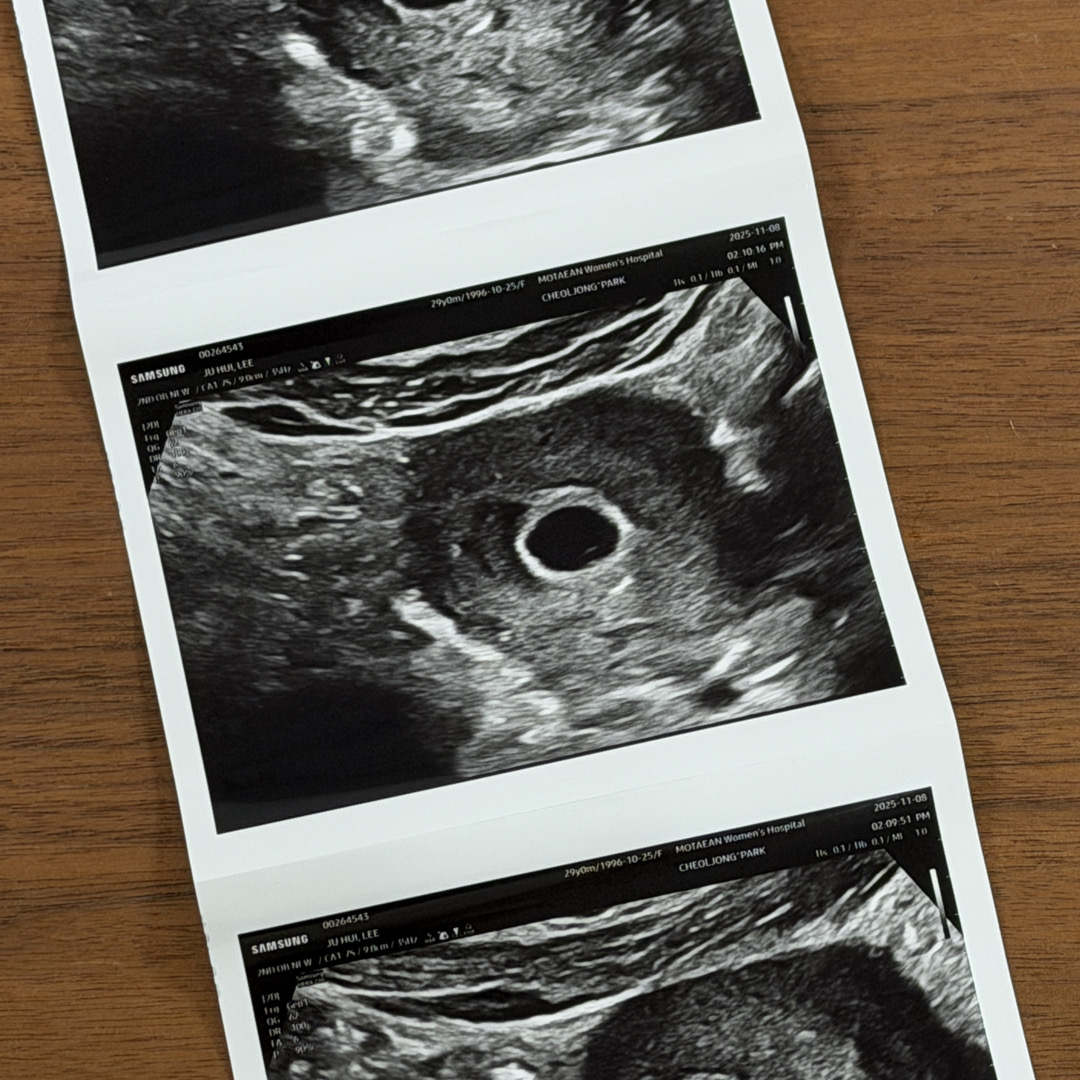

난황 동그랗게 보이는데 이제 막 생기기 시작한거 같아요! 일주일뒤면 예쁘게 자리 잡힐거예요

5주3일차 이구요! 첫 초음파봤는데 다른분들 보면 난황이 보통 반지모양? 링모양이라 들었는데 저는 점으로만 보여서 ㅠㅠ 괜찮은건가요??

5주차엔 난황이 아직 발달하지 않을 때라 반지모양으로 안 보여요 주수 좀 더 지나면 난황이 커지면서 아가와 함께 예쁜 반지를 보여줄거예요

보통 5주차엔 아기집 6주차쯤 되어야 난황 잘 보여요~~ 6주 후반~7주되면 아기 심장소리 들을 수 있고요 병원에서 별 말 안한거면 괜찮을거예요